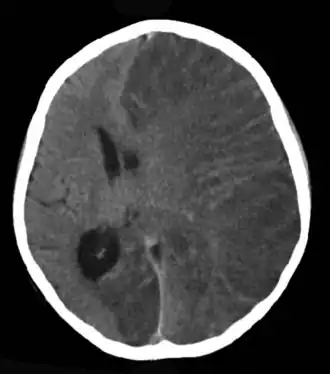

Scanner cérébral d'une personne présentant une encéphalite focale de Rasmussen.